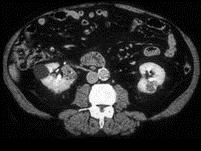

问题 男,54岁,无痛性血尿1个月余,请根据所示图像,选择最可能诊断 ( )

选项 A、右侧肾囊肿合并左侧肾癌 B、多发性肾癌合并肾囊肿 C、多囊肾 D、左侧肾癌并右肾转移 E、多发性肾囊肿

答案 B